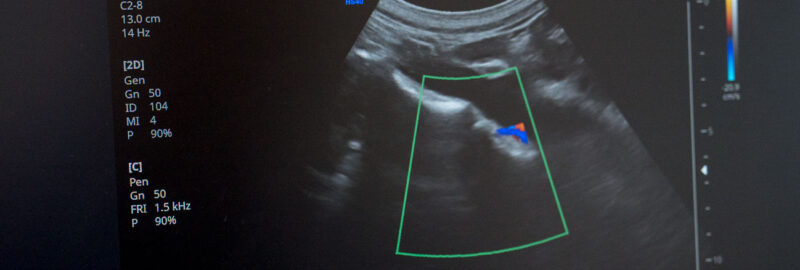

Esplora i nostri esami strumentali avanzati, tra cui eco-color-doppler, ecografia addominale e muscolo-tendinea, fornendo una valutazione precisa e dettagliata per una gestione efficace della tua salute.